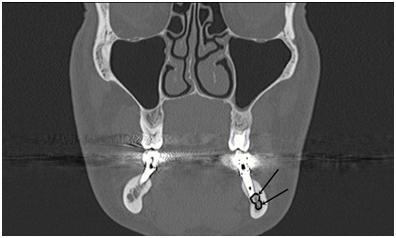

The subjects of this study consisted of 4 (2 male, 2 female) patients with an age range of 50–61 years with a mean of 55.25 years. In these 4 patients, the complaint was post‒surgical numbness in the lip and mucosal areas after implant operation between 8 and 12 months. The implants were seen to be related to the alveolar inferior nerve in post‒operative x‒rays (Figure 1). Patients participating in the present study do not have any previous neurological disorders.

Figure 1 Implants and Nervous Position in Orthophantogram.

In addition, the panoramic radiographs of Patient I showed the implant material and mandibular canal are close and there has seen bifid mental nerve (Figure 2). Ridge‒Split osteotomy was performed on alveolar bone and the implant was placed in the lower right 5th and 7th tooth regions to Patient I. In the Patient II two implants placed in mandibular molar region and numbness on the lip corner occurred in Patient I and II. At patient III and IV, there was numbness in the right lower jaw area and the mucosal area of canine teeth.

There is no consensus that CBCT scanning or CT effectively reduces IAN damage. Orthopantomography can be useful in implant planning.36 However, strict guidelines do exist enforcing the use of cross‒sectional imaging if required to better assess the IAN when routine radiography is inadequate.22 OPGs and other two‒dimensional radiographs have disadvantages to show the buccolingual aspect and cross‒sectional slices and patient positioning, magnification distortion and superposition of the anatomical structures.37,38 In our study, CT was taken after the procedure and there was a correlation between implant and nerve (Figure 1). In order to facilitate drilling efficiency, many implant drills are slightly longer than their corresponding implants and it is possible that the rate of nerve damage39,40 In this regard, it is important for the surgeon to be aware of the variations that exist in implant drill length. However, in patient III, the size of the implant used and the drill is same. It is estimated that the compression of the implant results in numbness at the lower right lip. Instead of surgical removal of the implant, not to lose implants, the patient was treated with LLT therapy. It is advisable to take an operation preliminary CT or prepare implant guide plates.